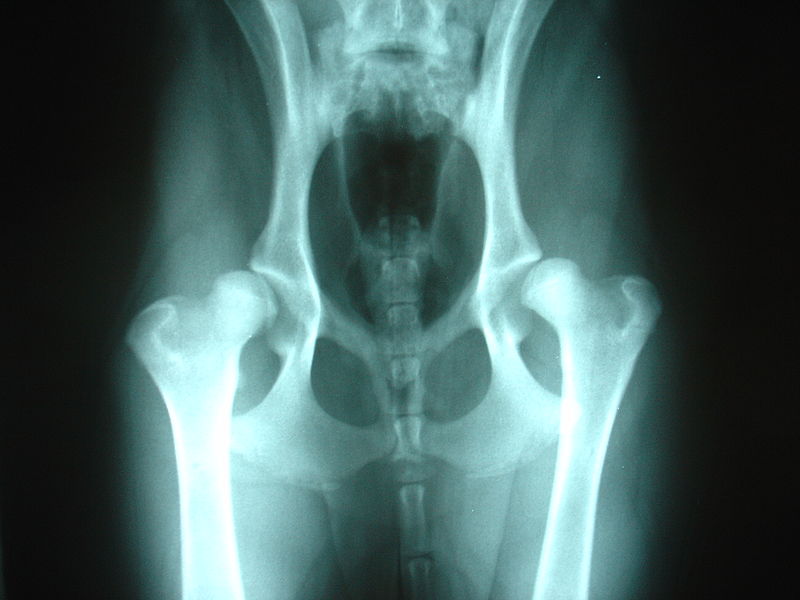

Đầu tiên các bạn nên xét nghiệm máu, chụp x-quang xem xương có bị biến dạng không, có bị thiếu canxi không. Sau khi có kết quả cụ thể thì tùy từng trường hợp mà bác sĩ sẽ đưa ra phương án điều trị hiệu quả nhất. Nên hạn chế vận động mạnh, cơ, khớp bị tổn thương làm giãn, rách dây chằng cần có thời gian nghỉ và thuốc men để phục hồi. Nên nhốt chuồng chỗ đủ sáng phần lớn thời gian để cún ngủ, nằm yên một chỗ, kết hợp một số loại thuốc hỗ trợ điều trị dưới sự hướng dẫn của các bác sĩ.

IV. Hỏng khung xương do loạn sản xương hông, loạn sản xương vai

1. Nguyên nhân và triệu chứng

Gần như ai nuôi chó cũng đã từng nghe đến những cụm từ này, đây là một trong những bệnh về xương khớp trên chó thường thấy. Nguyên nhân chủ yếu là do di truyền, một số ít mắc bện do chế độ dinh dưỡng, do môi trường, do vi sinh vật … Triệu chứng thấy rõ nhất là qua dáng đứng, hông hoặc vai khi đứng bị chụm lại thái quá, vận động thấy rõ sự khập khiễng ở hông và khớp đùi, tùy tình trạng năng nhẹ mà cún có thể liệt hẳn hoặc biến dạng hẳn dáng đi chân sau.

2. Điều trị